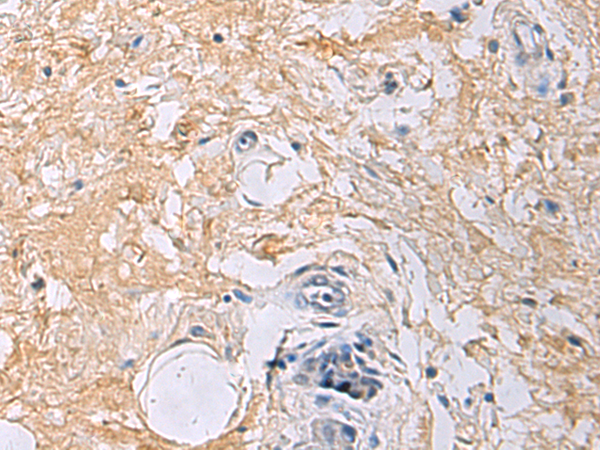

IHC positive control: |

Human gastric cancer |

IHC Recommend dilution: |

50-100 |